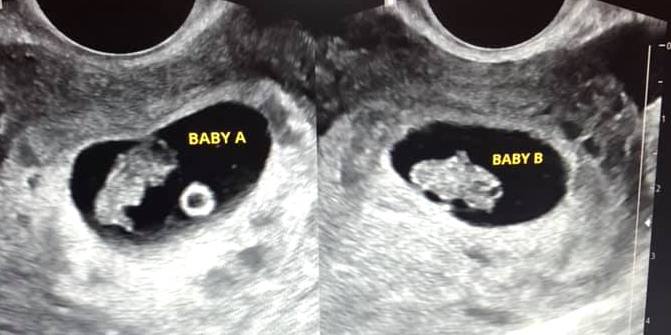

Early Twin Ultrasound at 7 Weeks

The earliest your doctor would likely order an ultrasound confirming twins would be 4 weeks pregnant. But unless you are going through fertility treatments, doing an ultrasound before 6 weeks isn’t very common, with the exception of complications. Women who are going through fertility treatments or have early complications may be able to have an early twin ultrasound at 4 or 5 weeks pregnant and find out they are pregnant with twins.

At four to five weeks after a pregnant woman’s last period the ultrasound commonly shows a small collection of fluid within the lining of the uterus that represents the early development of the gestational sac. At about five and a half weeks after a pregnant woman’s last period the ultrasound typically shows a gestational sac and within it we can see a 3-5 mm bubble-like structure, which is the yolk sac. At approximately six weeks after a pregnant woman’s last period, we can see a small fetal pole, one of the first stages of growth for an embryo, which develops alongside the yolk sac.

Can You Tell at 7 Weeks if Its Twins?

Yes! You’d need to have an ultrasound at 7 weeks to confirm a twin pregnancy. Your twin belly at 7 weeks may not look like much of a belly at all, so getting in to your doctor for an ultrasound is key to find out if you’re really having twins.